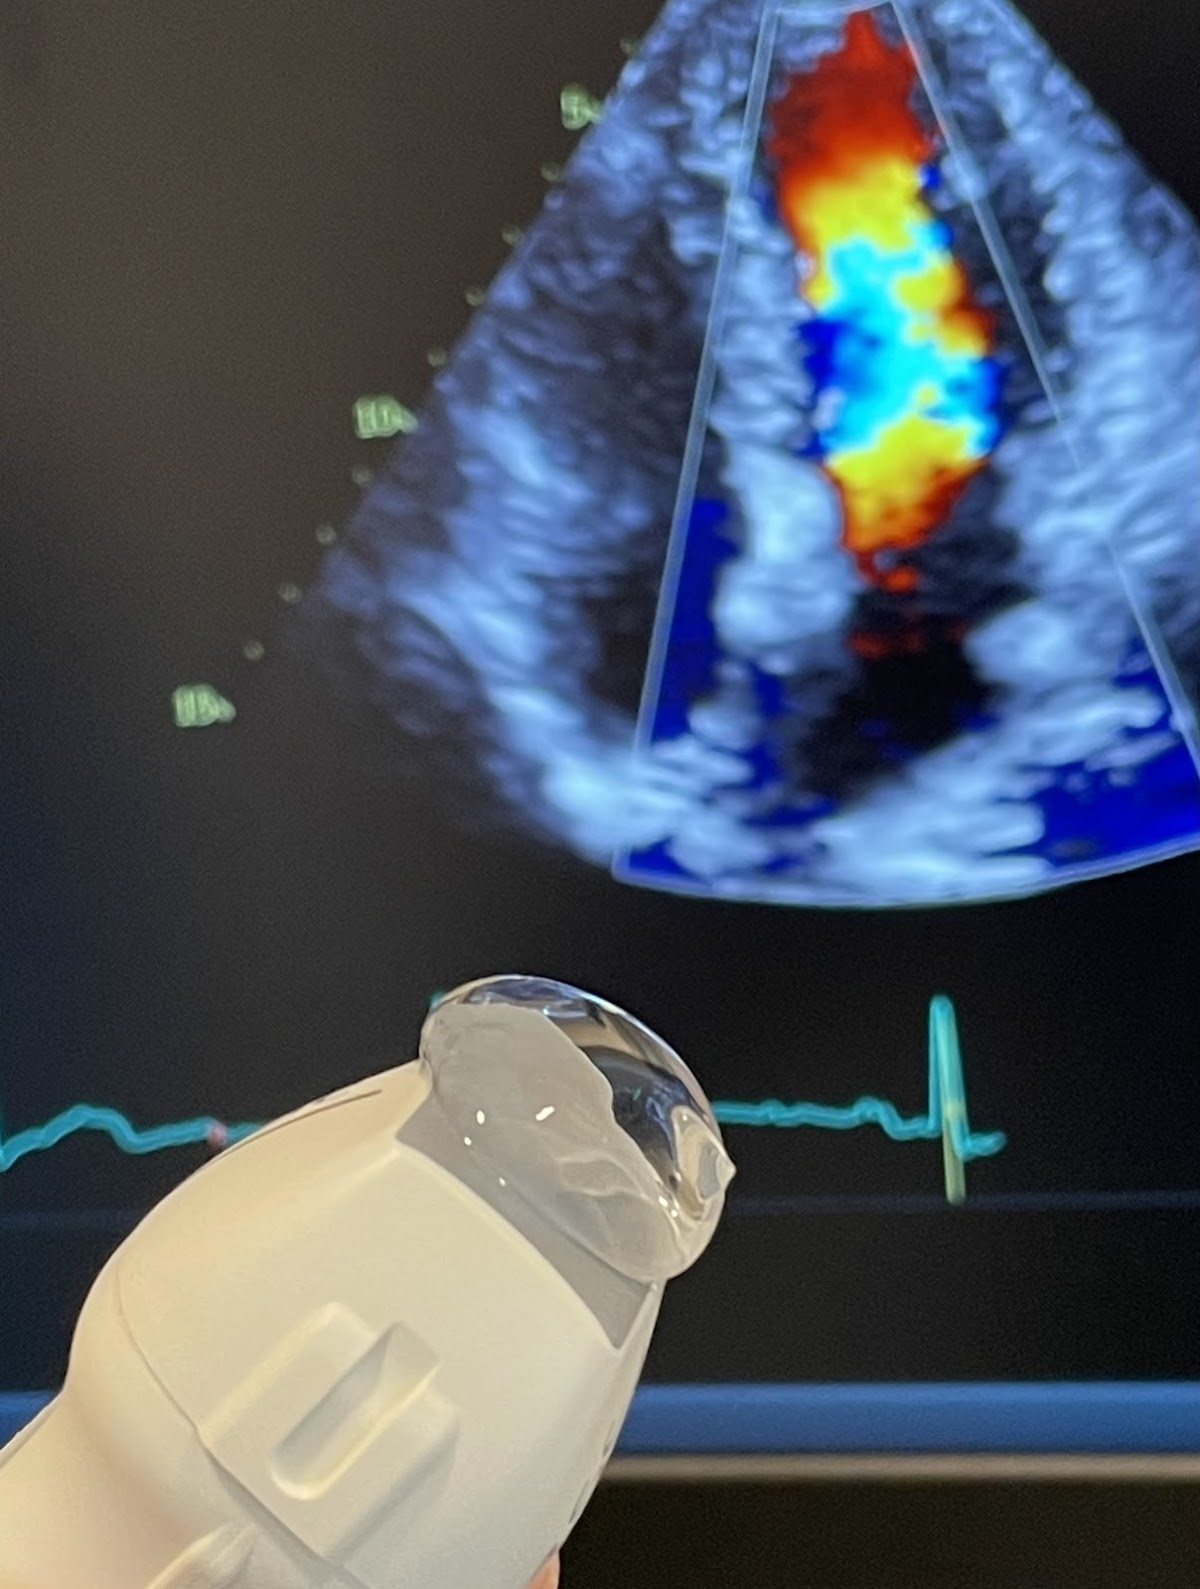

Their treatment menu covers a.treadmill ecg, b.echocardiography (heart ultrasound), c.24 hour holter ecg monitoring and d.24 hour ambulatory blood pressure monitoring, giving patients a broad range of options under one roof.